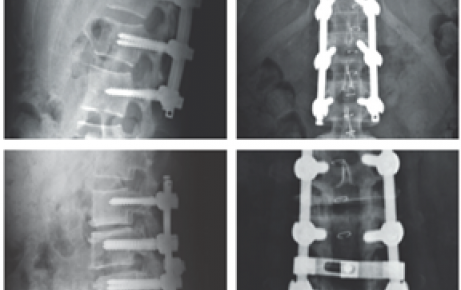

Orthotech (Hàn Quốc) là nhà sản xuất chuyên nghiệp trong lĩnh vực vật tư tiêu hao và dụng cụ phẫu thuật chỉnh hình, với nhiều năm kinh nghiệm nghiên cứu và phát triển sản phẩm phục vụ cho phẫu thuật xương khớp và chấn thương chỉnh hình. Các sản phẩm của Orthotech bao gồm kim, dây thép, nẹp, vít, dụng cụ hỗ trợ cố định xương và nhiều vật tư chuyên dụng khác, được sản xuất trên dây chuyền hiện đại, tuân thủ nghiêm ngặt các tiêu chuẩn quốc tế về chất lượng và an toàn.

Với mục tiêu mang đến giải pháp tối ưu cho bác sĩ và bệnh nhân, Orthotech không ngừng cải tiến thiết kế, nâng cao tính tiện dụng và độ chính xác của sản phẩm. Hiện nay, các sản phẩm của hãng đã được tin dùng tại nhiều bệnh viện và cơ sở y tế ở Hàn Quốc cũng như trên toàn thế giới.